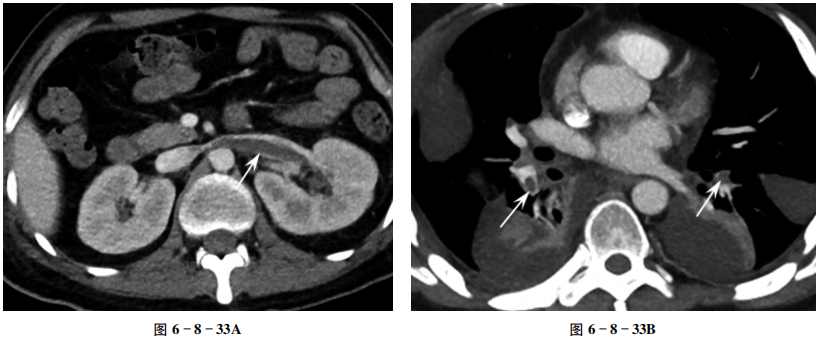

增强扫描髓质期左肾肿大,左肾静脉管腔内可见一无强化的长条状充盈缺损(箭头,图6-8-33A);两下肺动脉分支管腔内见不规则充盈缺损(箭头),两下肺见片状实变影,双侧胸腔积液(图6-8-33B)。

肾静脉充盈缺损。

肾静脉血栓,两下肺动脉分支血栓。

①急性肾静脉血栓:肾外形增大,肾实质强化减低,皮髓质分界不清,肾静脉扩张,内见条带状充盈缺损,可延伸到下腔静脉。②慢性肾静脉血栓:肾静脉纤细或充盈不均匀,可见钙化,肾周可见侧支血管,肾萎缩。③肾静脉属支(精索静脉、卵巢静脉、腰升静脉等)增粗迂曲,肾周“蜘蛛网”样静脉扩张。本例为肾静脉血栓急性期。